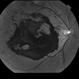

- hemicentral retinal vein occlusion, collaterals, retinal neovascularization

- Initial presentation: 25-year-old AAM; Hx DM, Sarcoidosis, Renal Disease, HTN with recent hypertensive crisis. Collateral vessels likely due to old HRVO with one front of NVE inferiorly; veins attenuated proximal to the collateral vessels.